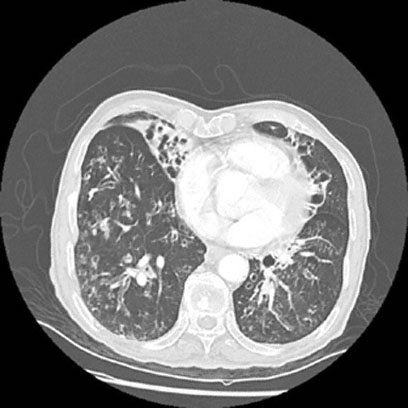

A 72-year-old man is brought to the emergency department 30 minutes after the sudden onset of severe chest pain that radiates to his back. Ten years ago, he underwent coronary artery bypass grafting after he sustained a myocardial infarction. Since then, he has had intermittent substernal chest pain. He has hypertension and is not always compliant with his medication regimen. Medications include a nitrate, calcium-channel blocking agent, and β-adrenergic blocking agent. He appears anxious and diaphoretic and is unable to find a comfortable position. His temperature is 37.9°C (100.2°F), pulse is 65/min and regular, respirations are 30/min, and blood pressure is 190/110 mm Hg on the right and 110/80 mm Hg on the left. The lungs are clear to auscultation. No gallops or murmurs are heard. A CT scan of the chest shows an opacification of half of the aortic lumen from just proximal to the origin of the left subclavian artery and extending to the celiac artery distally; there is a thrombus in the aortic false lumen and a left pleural effusion. Which of the following is the most appropriate next step in management?

A 52-year-old woman comes to the physician as a new patient because of a 5-day history of temperatures to 38.2°C (100.8°F) and cough productive of thick, gray-green sputum. She says the sputum is difficult to cough up. During the past 15 years, she has had similar symptoms twice yearly, which resolved after treatment with antibiotics. Because of lack of insurance during this time, she was treated at urgent care clinics. She has no known allergies and no history of serious illness. Her only medication is an over-the-counter cough suppressant. She does not smoke cigarettes or use illicit drugs. She drinks three glasses of wine weekly. She is 170 cm (5 ft 7 in) tall and weighs 91 kg (200 lb); BMI is 31 kg/m2. Her temperature is 38°C (100.4°F), pulse is 80/min, and blood pressure is 138/84 mm Hg. Pulse oximetry on room air shows an oxygen saturation of 94%. On pulmonary examination, there is an increased expiratory phase; rhonchi and faint wheezes are heard bilaterally. A CT scan of the chest is shown. Which of the following is the most likely diagnosis?